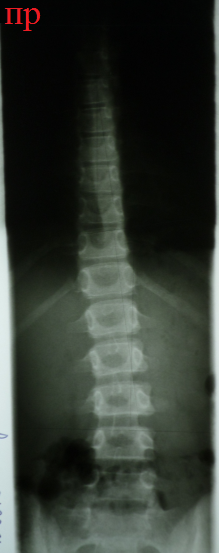

Снимки

позвоночника ребенка с идиопатическим сколиозом в возрасте 12 и 14 лет (справа

– слева соответственно). На снимке в 12 лет определяется компенсированная С - образная

деформация позвоночника в области верхней части поясничного – нижней части

грудного отделов. Признаки ротации позвонков в области дуги – тени ножек дуг

смещены от центральной линии тел позвонков. На снимке в возрасте 14 лет

определяется S - образная деформация

позвоночника, потому что сформировалась компенсаторная дуга 5° в грудном отделе. Смещение теней ножек дуг

относительно центральной линии тел

позвонков стало еще больше, что говорит о том, что структурные изменения в

позвонках увеличились. При этом нарастание угла деформации основной дуги

составило всего лишь 3 градуса.

Интересно, что в конкретном

примере Slide – Shift

и вершина дуги направлены влево.